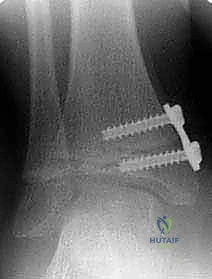

الخطوة الرابعة: تثبيت الشريحة (8-Plate)

بمهارة فائقة، يقوم الدكتور هطيف بوضع الشريحة المعدنية المصنوعة من التيتانيوم الطبي النقي فوق مركز النمو. يتم تثبيت الشريحة باستخدام مسمارين صغيرين؛ أحدهما فوق خط النمو والآخر تحته. هذه المسامير لا تخترق مركز النمو نفسه، مما يضمن عدم تدميره.

الخطوة الخامسة: الإغلاق التجميلي

يتم إغلاق الجرح بخيوط تجميلية تذوب من تلقاء نفسها، ويوضع ضماد طبي خفيف. لا يحتاج الطفل إلى وضع جبس أو قوالب صلبة بعد العملية، وهو ما يمثل ميزة هائلة لهذه التقنية.

- إزالة الشريحة: بمجرد أن يستقيم الكاحل ويصل إلى الزاوية الطبيعية المثالية (غالباً بعد 6 إلى 12 شهراً)، يتم إجراء عملية جراحية صغرى وسريعة جداً لإزالة الشريحة والمسامير، ليُترك الطفل بقدم سليمة ومفصل طبيعي تماماً.